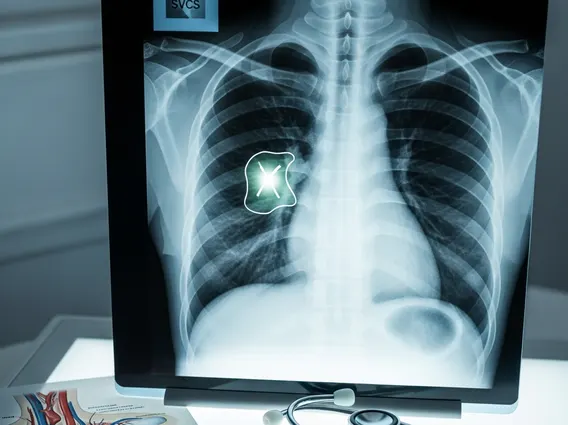

- Malignant tumors, particularly lung cancer, are the most frequent cause of SVCS.

The primary **Superior Vena Cava Syndrome causes** are often related to malignancy, accounting for approximately 80-90% of cases. Lung cancer, particularly small cell lung cancer, is the most common malignant cause, followed by non-Hodgkin lymphoma and metastatic cancers that spread to the mediastinum (the area between the lungs). These tumors can directly compress the SVC or invade its wall.

Non-malignant causes, though less common, are also significant. These include benign tumors, mediastinal fibrosis, and increasingly, intravascular devices such as central venous catheters, pacemakers, and defibrillator leads, which can lead to thrombosis (blood clot formation) within the SVC. The presence of these devices can irritate the vessel wall, predisposing it to clot formation and subsequent obstruction.